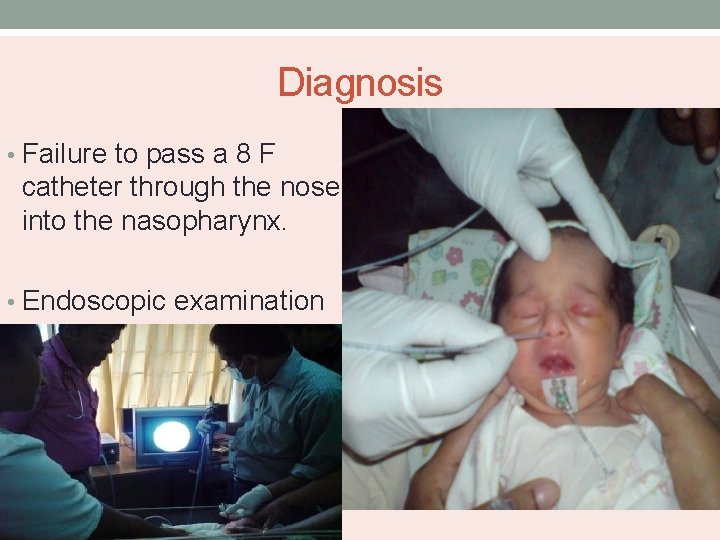

Diagnosis • Failure to pass a 8 F catheter through the nose into the nasopharynx. • Endoscopic examination